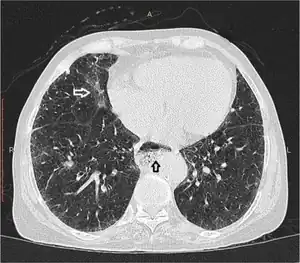

Esophageal dysmotility black arrow